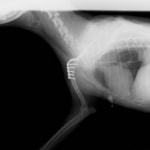

■ミニチュアダックスフント 1歳 去勢オス

前肢の成長板早期閉鎖、前肢の重度の外反変形が認められました。

関節面の変形が重度に認められます。